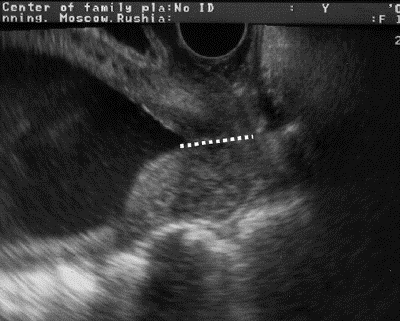

Снимок с УЗИ шейки матки

Видно ли данную патологию на УЗИ

УЗИ при эрозии можно проводить двумя способами – через кожное обследование и обследование с введением датчика во влагалище. Девственницам и беременным женщинам второй вариант не назначают.

Лучше всего рассмотреть эрозию возможно при внутреннем введении датчика. Данное обследование позволяет провести оценку слизистой, осмотреть ее клеточный состав, а также определить размеры и толщину.

Кроме того, вагинальное УЗИ покажет, как поврежденные ткани снабжаются кровью.

Всегда ли на УЗИ видно эрозию? Нет. Как правило, визуализировать эрозию при помощи УЗИ можно только в том случае, если заболевание уже находится в запущенной стадии.

Легкие и умеренные формы эрозии не приводят к значительным изменениям, поэтому их увидеть при помощи аппарата УЗИ достаточно проблематично. Кроме того, возможны погрешности, поэтому если врач предположил наличие эрозии, он отправляет пациентку на дополнительное обследование.